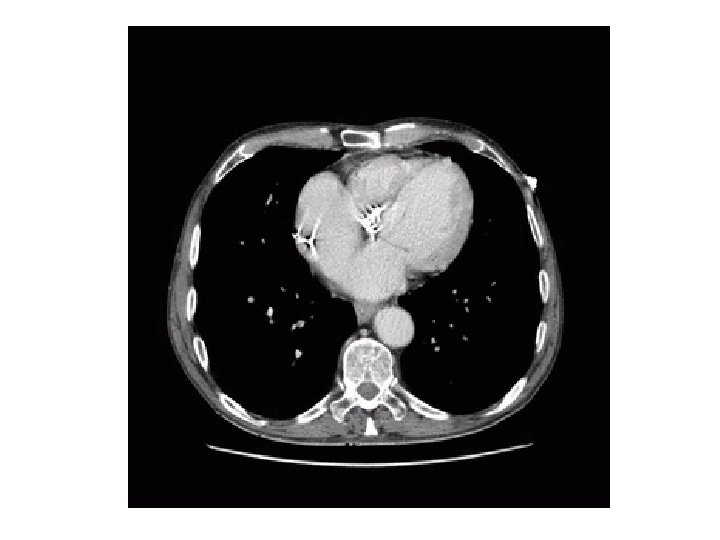

Mr T • Patient de 76 ans consultant aux urgences • Syndrome douloureux abdominal évoluant depuis 10 jours , majoration des symptômes depuis 3 jours • Fièvre à 38. 5°C, frissons et vomissements • Abdomen dépressible mais douloureux en fosse iliaque gauche • Hyper leucocytose à 17 000/mm 3, CRP à 115 Recherche de sigmoïdite

Qu’en dites vous? • Sigmoïdite • Abcès au contact d’anses grêles • Perforation digestive • Anévrisme de l’aorte

Quel est votre diagnostic? • Collection hétérogène au contact de l’intestin grêle associé a la présence d’un pneumopéritoine localisé • Diagnostic positif: perforation grêlique avec abcès au contact

Quel est votre diagnostic? • Diagnostic étiologique: – Vaisseaux perméables, absence de défaut de rehaussement, absence de syndrome occlusif mécanique – Absence d’épanchement, d’épaississement pariétal, de sténose, de diverticule – Corps étranger peu dense

Imagerie TDM • Signes de perforation – Direct: interruption de paroi – Indirect: pneumopéritoine, infiltration de la graisse, épaississement de la paroi digestive – Elle peut être ouverte ou couverte • Bilan étiologique – Occlusion mécanique, ischémie mésentérique, Crohn, lymphome, diverticulite, tuberculose, ulcère jejunal, vascularites, corps étranger